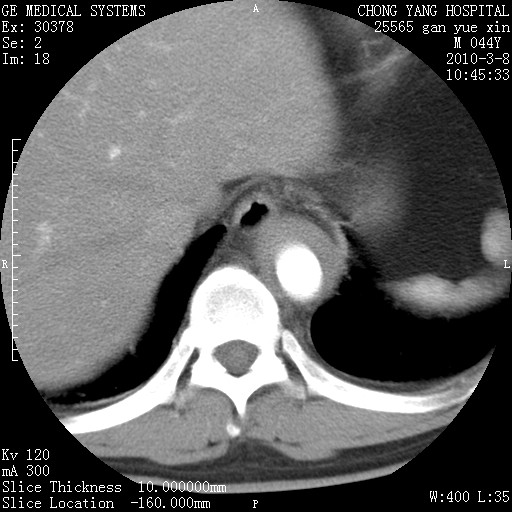

标题: CT24940:主动脉增强,典型病例。 [打印本页]

标题: CT24940:主动脉增强,典型病例。

夹层动脉瘤。

动脉夹层

夹层动脉瘤,典型

主动脉夹层。

动脉夹层的分型:

⒈debakey分型:根据主动脉夹层累及部位,分为三型:ⅰ型:原发破口位于升主动脉或主动脉弓部,夹层累及升主动脉、主动脉弓部、胸主动脉、腹主动脉大部或全部,少数可累及髂动脉。ⅱ型:原发破口位于升主动脉,夹层累及升主动脉,少数可累及部分主动脉弓。ⅲ型:原发破口位于左锁骨下动脉开口远端,根据夹层累及范围又分为ⅲa,ⅲb。ⅲa型:夹层累及胸主动脉。ⅲb型:夹层累及升主动脉、腹主动脉大部或全部。少数可累及髂动脉。

⒉stanford分型:a型:夹层累及升主动脉,无论远端范围如何。b型:夹层累及左锁骨下动脉开口以远的降主动脉。

夹层动脉瘤,少量胸水

夹层动脉瘤;左侧少量胸腔积液。

典型主动脉夹层。